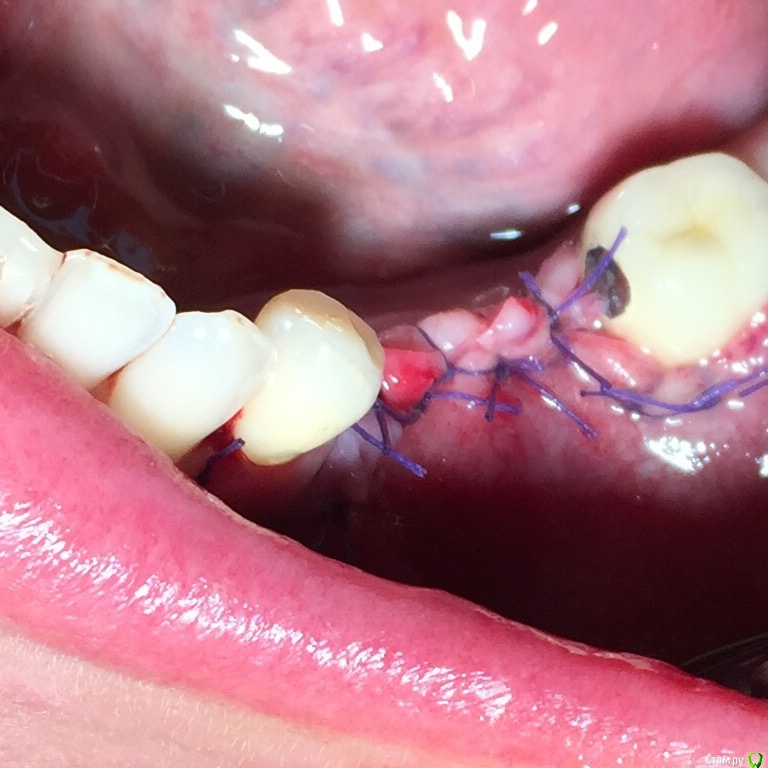

alekszander Опубликовано 12 сентября, 2015 Поделиться Опубликовано 12 сентября, 2015 Прошу прощения, но ушили как то в натяг (по фото) или ошибаюсь? Делали мобилизацию лоскута? Ну и швы грубовато очень. А так спасибо мне познавательно расщепление посмотреть. 1 Ссылка на комментарий

Глеб Митрофанов Опубликовано 12 сентября, 2015 Автор Поделиться Опубликовано 12 сентября, 2015 Прошу прощения, но ушили как то в натяг (по фото) или ошибаюсь? Делали мобилизацию лоскута? Ну и швы грубовато очень. А так спасибо мне познавательно расщепление посмотреть. Мобилизация была, лоскут свободно перекрыл поле , швы двумя этажами , матрацные выворачивают края , поэтому вид грубости создаётся . 1 1 Ссылка на комментарий

k.t.m. Опубликовано 17 сентября, 2015 Поделиться Опубликовано 17 сентября, 2015 а чем вам викрил не нравиться объясните пожалуйста лично я не использую викрил при обьемных(ключевое слово) нкр, по тому что есть набухание и контаминация плетенки нитей,и если есть риск контакта нитей с графтом,мембраной с вытекающими ,то я пытаюсь риски свести к минимуму. 4 Ссылка на комментарий